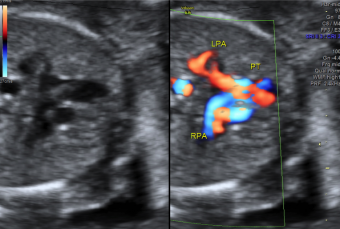

Ecocardiografia fetală este o etapă importantă a examinarii anatomiei fetale – anomaliile cardiace sunt cele mai frecvente malformatii congenitale (în imagine bifurcația trunchiului a. pulmonare).